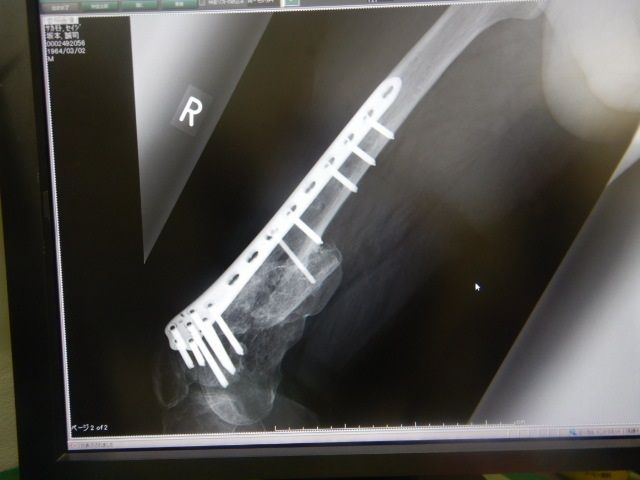

±¦ÂȾǯÄê´ü·ò¿Ç

Ⱦǯ¤Ë°ìÅ٤α¦ÂÄê´ü·ò¿Ç¤¬ºòÆü¤Î·îÍËÆü¤À¤Ã¤¿¤Î¤Ç

ÆóÏ¢µÙ¤Ë¤Ê¤ê¤Þ¤·¤¿¤¬Î×»þµÙ¶È¤ò夤¤ÆÉ±¡¤Ø

¿Í¸ý¹ü¤â¤«¤Ê¤ê¤¯¤Ã¤Ä¤¤¤Æ¤¤Æ¤Þ¤¹¤¬

¥×¥ì¡¼¥È¤Î½üµî¤ÏºÆ¹üÀޤΥꥹ¥¯¤¬

¤¢¤ë»ö¤«¤é½üµî¤·¤Ê¤¤Êý¸þ¤Ç¤¹¡£¤Ç¤âÅߤˤʤë¤È¥×¥ì¡¼¥È¤¬Î䤨¤Æ

Äˤ¤¤ó¤Ç¤¹¤è¤Í¤§¡Ä

¤Þ¤¡»ÅÊý¤¬¤¢¤ê¤Þ¤»¤ó¡£